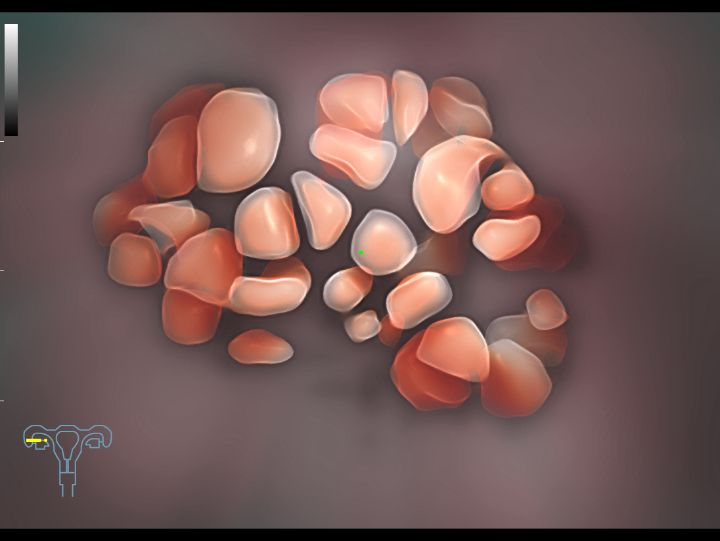

Pelvic ultrasound is considered as the first choice of imaging examination method to evaluate suspected gynecological diseases in women of all ages. Ultrasonography is usually the only necessary imaging examination to diagnose uterine, ovarian and adnexal diseases because of its wide availability, low cost and advantages of no ionizing radiation. With the development of volume ultrasound technology, 3D ultrasound has become a routine gynecological examination item. Through the acquisition of volume data, 3D ultrasound can display the uterus, cervix, ovary and uterine adnexa on any plane, and has more advantages in evaluating the uterine cavity.

UWN+ CEUS provides excellence contrast agent sensitivity and image penetration to get more diagnosis information for gynecology tumor or other difficult diseases. Also MindrayŌĆÖs STE (Sound Trouch Elastogtaphy) can quantitatively evaluate tissue stiffness which is helpful for previse diagnosis of difficult uterus, cervix and ovary diseases.